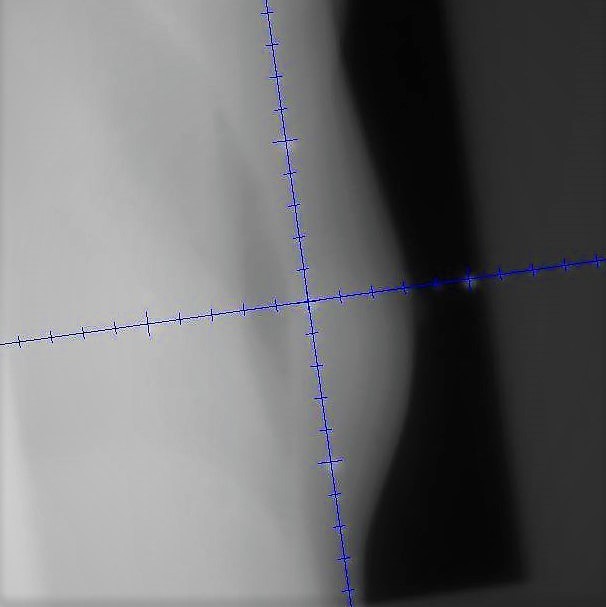

以下は乳房と前立腺の照射で位置が合っていることを確認している画像です。